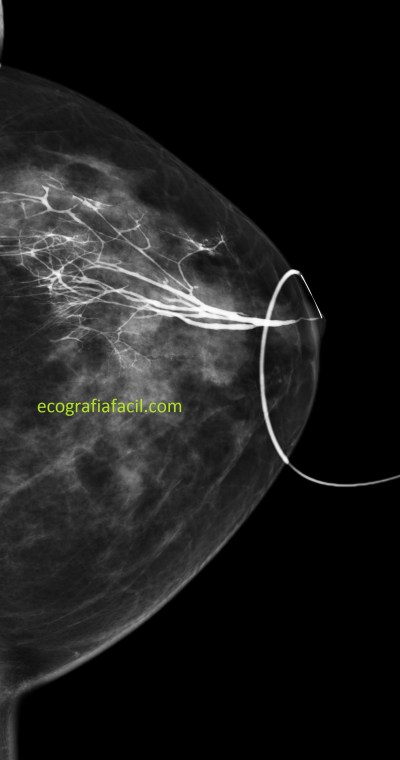

He comentado antes que en ocasiones se le puede realizar a una paciente una galactografía, sobre todo cuando la secreción es por un solo conducto, y además sanguinolenta, pero es decisión de las doctoras, como ya he comentado. Esta prueba es la Galactografía, antes era muy habitual su realización, cada día más en desuso, te dejo la imagen 9 para que aprecies la belleza de esta técnica donde se usa un contraste que se inyecta previa canalización del agujero correspondiente al conducto que tiene la secreción, usando el mamógrafo para esta técnica.

Imagen 9 e imagen 10 son dos técnicas diferentes, que guardan una correlación muy evidente en la representación de los conductos galactóforos que van a buscar el pezón.